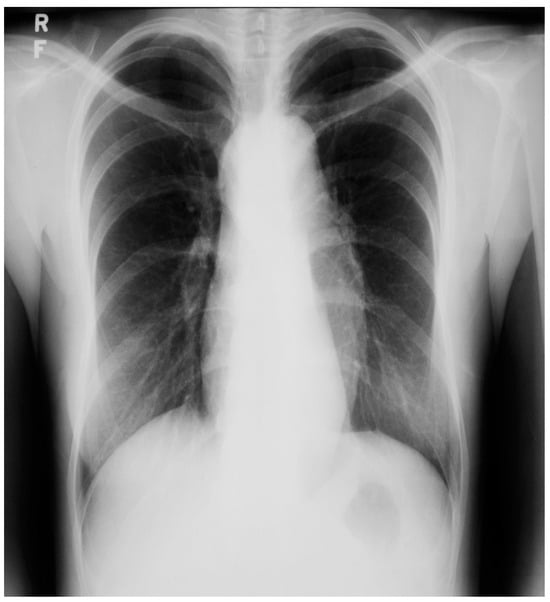

Figure 23.

Posteroanterior chest X-ray in an adult with previously operated tetralogy of Fallot: the chest X-ray was obtained in a 21-year-old female with exertional dyspnea. She was cyanotic at birth and diagnosed with tetralogy of Fallot. She had a Blalock-Thomas-Taussig (BTT) shunt (palliative subclavian artery to pulmonary artery shunt) at 10-months-of-age. At 3-years-old she underwent complete repair with closure of the ventricular septal defect, right ventricular (RV) outflow tract reconstruction with pericardium, with transannular patch and ligation of the BTT shunt. This posteroanterior chest X-ray is well centered and the inspiration is good. The cardiothoracic ratio is increased and the cardiac silhouette is boot-shaped (“coeur en sabot”). The right heart border is prominent, suggesting right atrial enlargement. The pulmonary vascularity is normal and the lung fields and pleura are clear.